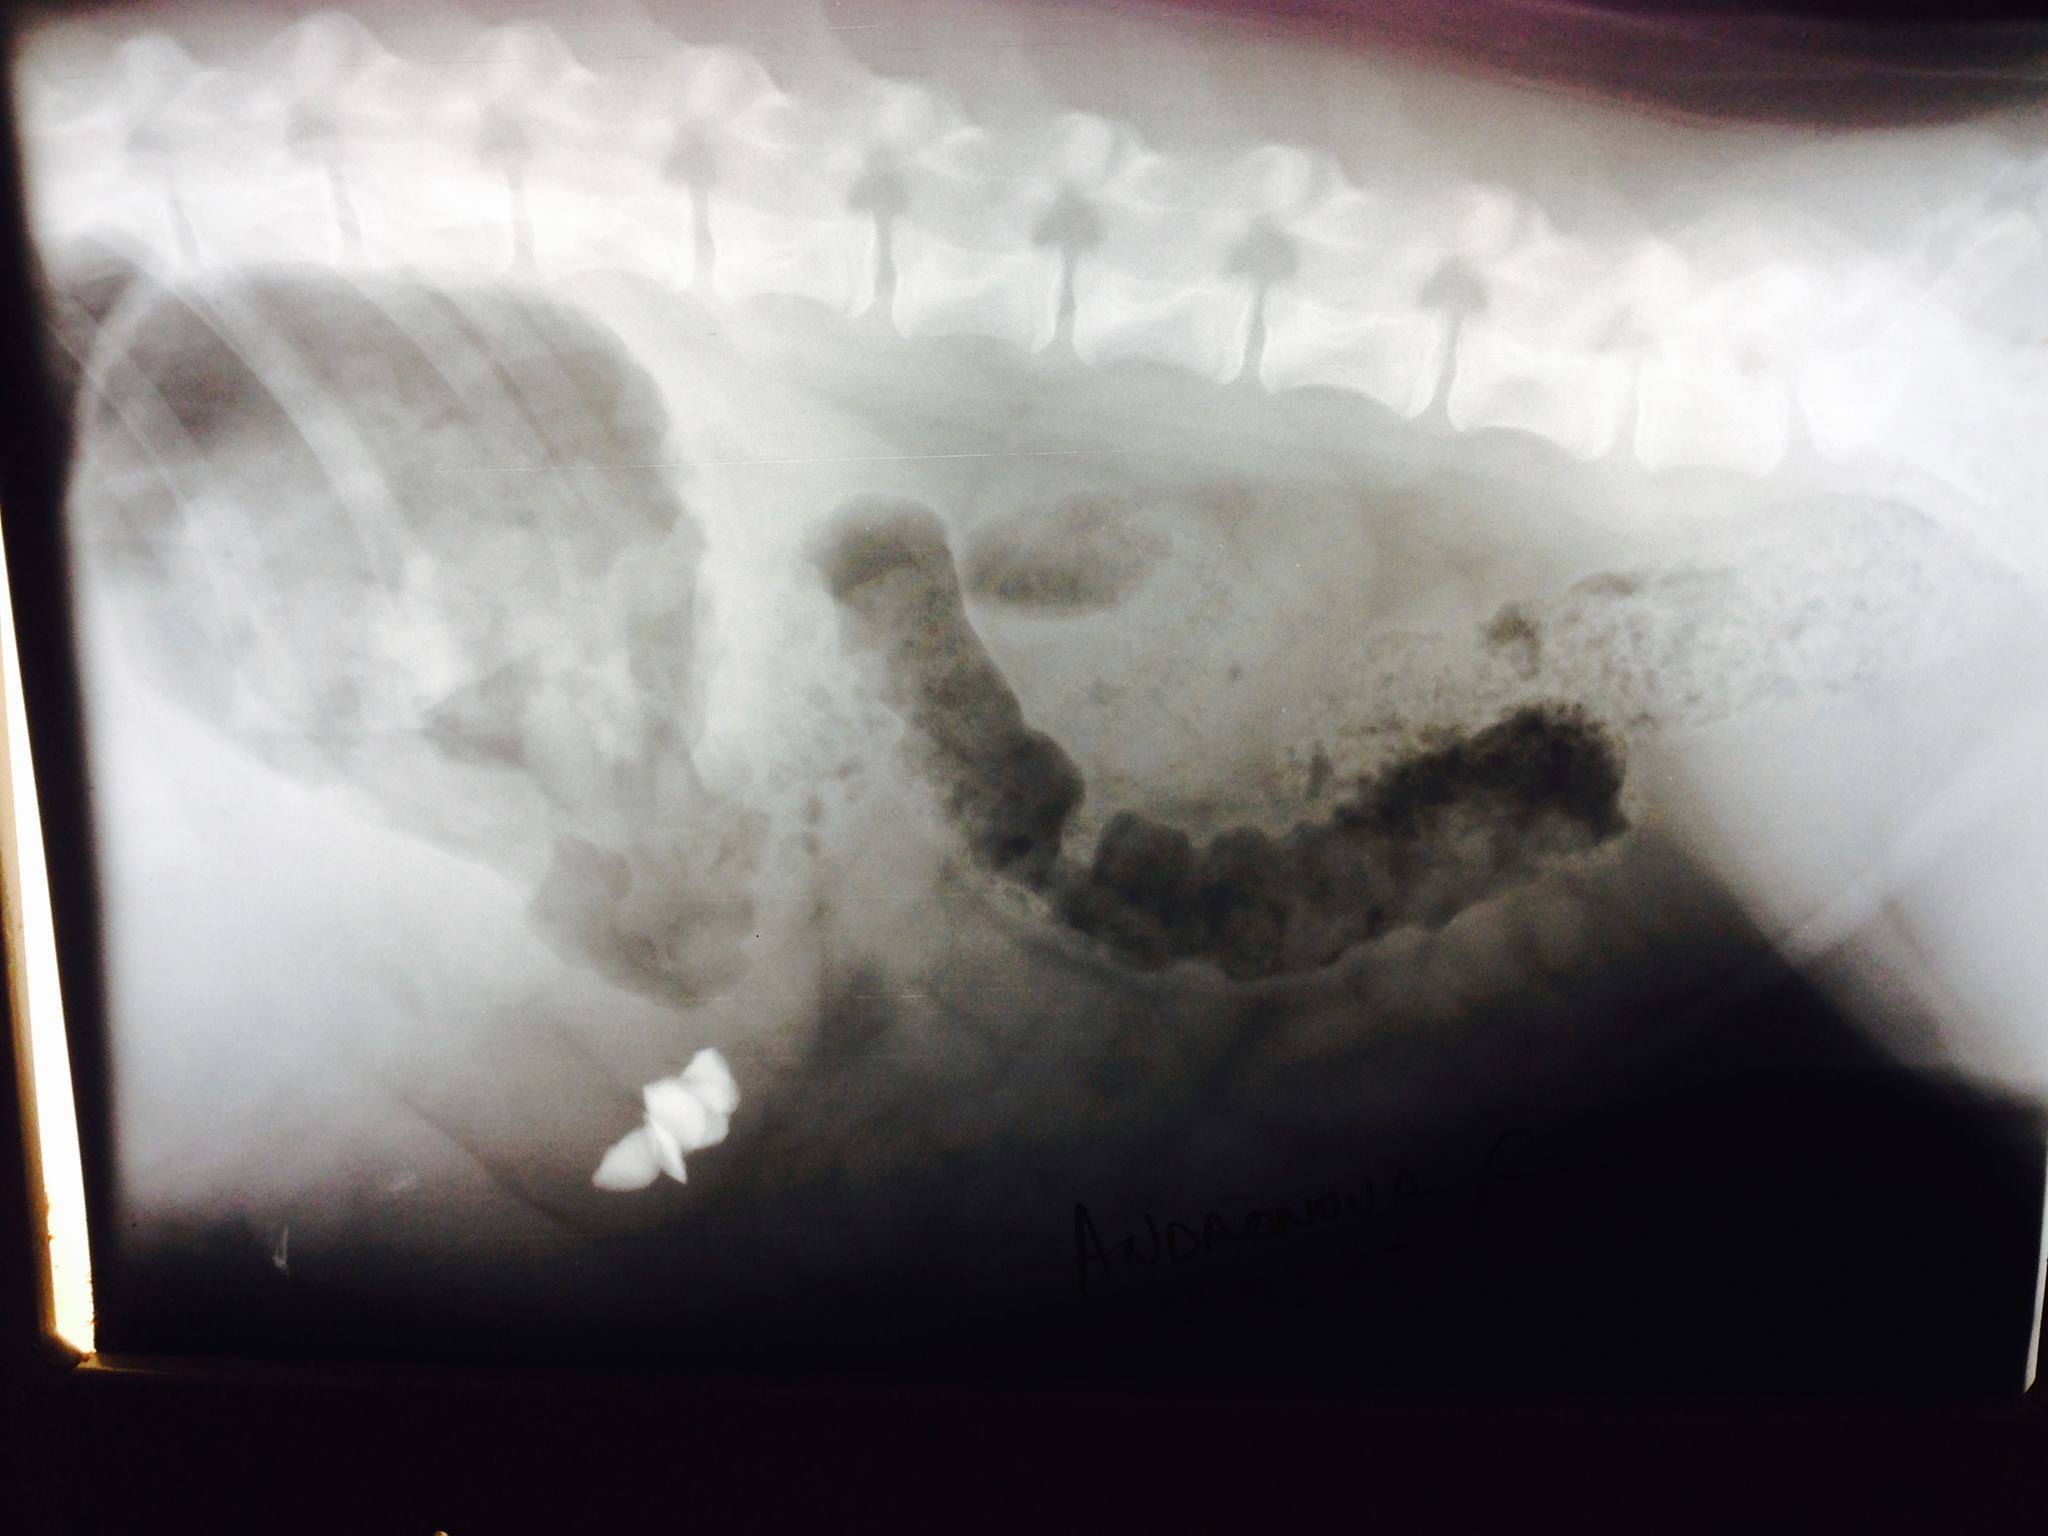

Рентген.

Застрявшие в пищеводе камни у одного из моих щенков.

Нажмите на изображение для увеличения

Название: 14393788_1172391506167260_1703969545_o.jpg

Просмотров: 217

Размер:	159.1 Кб

ID:	85688